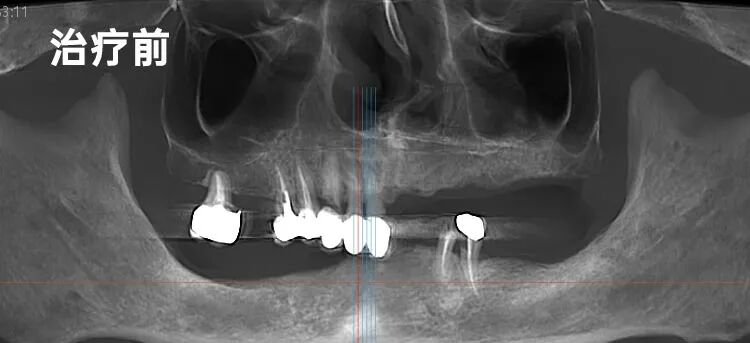

经李院长详细检查,问题远比想象复杂:全口余牙需拔除,而下颌后牙区的骨高度严重不足——“就像想在沙滩上盖高楼,地基却不够深。”这对种植而言是巨大挑战。更棘手的是,谭先生对看牙有着根深蒂固的恐惧,复杂的病情让他多年裹足不前。

“谭先生,别担心。咱们的方案好比盖一栋特别稳当的房子,虽然地基条件需要处理,但我们有专门的‘加固’技术。”他用盖楼的比喻,将“下颌种植4颗马龙桥修复,上颌6搭6即刻修复”的综合方案娓娓道来,复杂的技术被拆解成听得懂、摸得着的步骤。